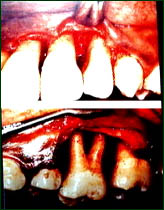

主持人:是不是只有成年人才容易得牙周炎? 沙月琴:这种观点是错误的。3岁的儿童就可以得牙龈炎,5岁的儿童就可以得牙周炎,临床上我们也确实看到过3岁半的孩子得了很重度的牙周炎,所以从幼儿开始就应该关注孩子的牙周健康。 章锦才:青少年牙周炎的发病率明显比中老年人要低得多,但是一旦发病就会十分严重。如图:从外观上看牙龈并没有十分红肿的症状,手术过程中翻开牙龈可以看到牙槽骨已经破坏得非常严重了,患者是因为觉得牙齿开始松动了,才来到医院看病的,到医院后医生通过牙周探测器探察后发现牙周带已经很深了,然后用照X片就看到了牙槽骨的异常情况。